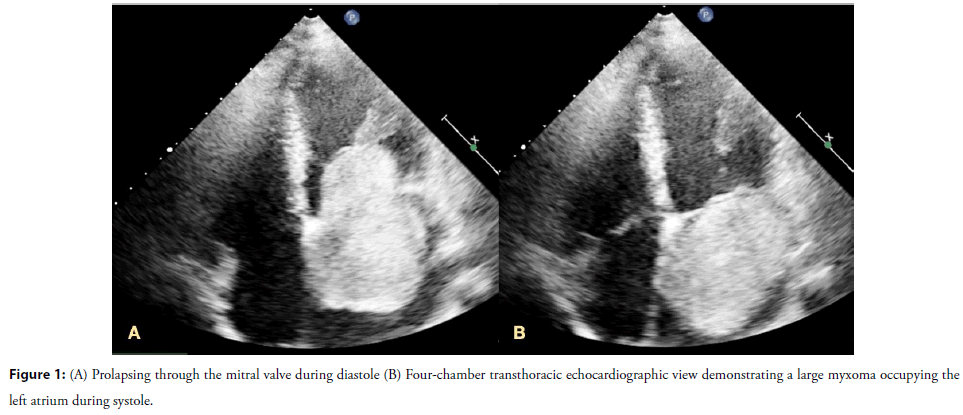

Transthoracic echocardiography identified a large, heterogeneous, and highly mobile intracavitary mass occupying a substantial portion of the left atrium during systole. The lesion measured 83 Ã 46 mm, corresponding to an estimated surface area of 37 cm2. It was attached to the interatrial septum by a pedunculated stalk and prolapsed through the mitral valve into the left ventricle during diastole. Notably, there was no significant transmitral gradient, and only mild mitral regurgitation was observed. Mild tricuspid regurgitation was present, with preserved right ventricular function and normal pulmonary arterial pressures (Figure 1, Video 1).

Video 1: Echocardiographic video in a four-chamber view illustrating the large left atrial myxoma prolapsing through the mitral valve during each diastolic phase.